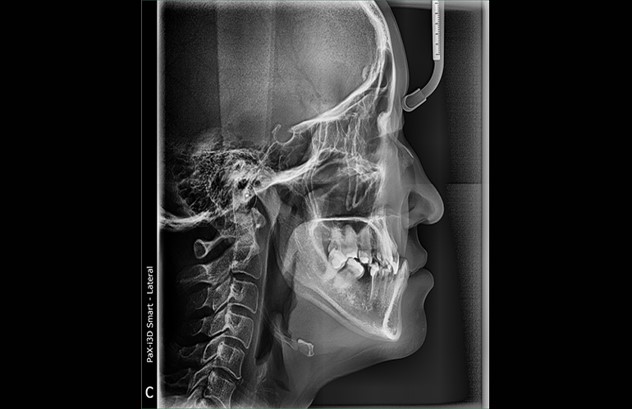

Бид рентген зураг дээр үндэслэн хүүхдийн шүдний эмчилгээг хийдэг бөгөөд хүүхдийг айдас, өвдөлтгүй эмчилж, үйлчилж байна.